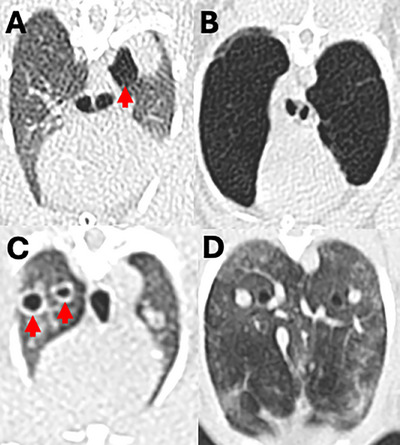

Pulmonary emphysema (PE) is a poorly understood condition in rabbits. This retrospective case-control study investigated the CT and clinical findings of rabbits with PE. Institutional archive review identified 724 thoracic CT studies of 529 rabbits, including 76 PE-positive studies of 59/529 rabbits. Twenty-five PE-negative cases were selected randomly as a control group. The mean age of affected rabbits was 9 years (range 5-13 years). Cranial lung lobes were more commonly affected (p < .01). The X-ray attenuation in Hounsfield units (HU) of the emphysematous lung areas (median -905 HU) was significantly lower than in nonemphysematous lung lobes of the case (median -667 HU) and control group (median -652 HU). There was significantly lower X-ray attenuation in peripheral and bullous emphysema than in diffuse emphysema. There was no statistical correlation between clinical lower respiratory signs and PE presence. However, the small portion (n = 6, 10.2%) of affected rabbits with severe respiratory signs, such as open-mouth breathing and cyanotic mucous membranes, all had advanced PE and poor outcome. Secondary changes attributable to PE included pathologic rib fractures in 3 (5.1%) and bulla rupture leading to pneumothorax in 2 (3.4%) rabbits. Of the 15 rabbits with repeat examinations, PE was progressive in 12 (80%) and static in 3 (20%). PE is a common condition in rabbits that is readily detectable with CT. The progressive nature of PE should be considered when detected in asymptomatic rabbits. In rabbits with severe lower respiratory signs, PE should be considered as a potential cause.